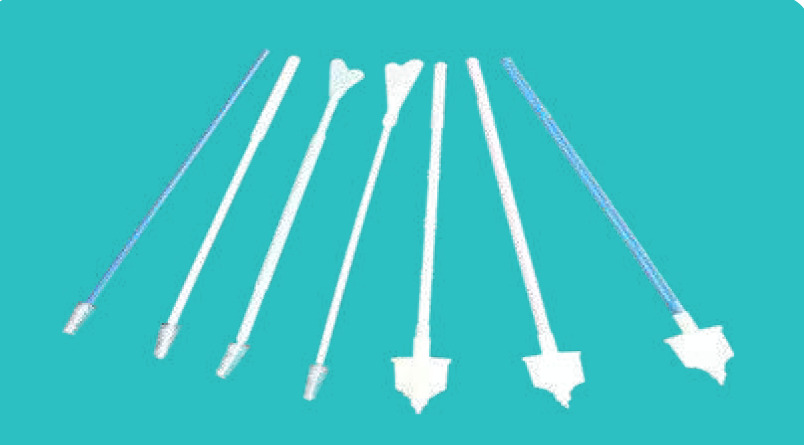

Vaginal Speculum

Description: It can be used for the checking and treatment of gynecology disease in hospitals or clinics. Before using it, user must read the usage manual, and then take the speculum, push the “duckbill” of speculum that is closed into the vaginal slowly.

Open the “duckbill” of speculum according to demand, fix the nut of speculum, then it can be used for checking and treatment of gynecology disease. After all, loose the nut of speculum, and take “duckbill” of speculum out of the vaginal slowly.

Specification:

Material: Polystyrene, transparent substance, non-toxic, medical grade.

Size: Large, Medium, Small.

Sterilization: EO.

Packing: Steriled in individual polybag or Film+Polybag or Blister pack, 100pcs/ctn.

Carton Size: 520x380x360mm G.W: 7kgs N.W: 6kgs

Disposable Vaginal Speculum With Side Screw

Disposable Vaginal Speculum French Type

Disposable Vaginal Speculum Spanish Type

Disposable Vaginal Speculum With Middle Screw

Disposable Vaginal Speculum Australia Type

Disposable Vaginal Speculum South Asian Type

Cervical Rambrush

Usage: Sampling Examination For Male And Female

Material: Stainless Steel Thread + PVC Handle + Nylon Tip

PVC Model: Slid Type, Injection Type

Packing: 1pc/blister bag

Carton Size: Normal Type 5000pcs/ctn 41x35x14cm

Broom Type 4000pcs/ctn 44x43x37cm